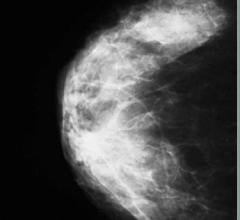

The women’s health channel includes news, videos, podcasts and other content related to technology used to detect and treat breast cancer and cervical cancer, including mammography, breast magnetic resonance imaging (MRI), automated breast ultrasound (ABUS), breast ultrasound, breast biopsy and breast radiation therapy.

Sept. 10, 2012 — High mammographic breast density, which is a marker of increased risk of developing breast cancer, does ...

Despite decades of progress in breast imaging, one challenge continues to test even the most skilled radiologists ...